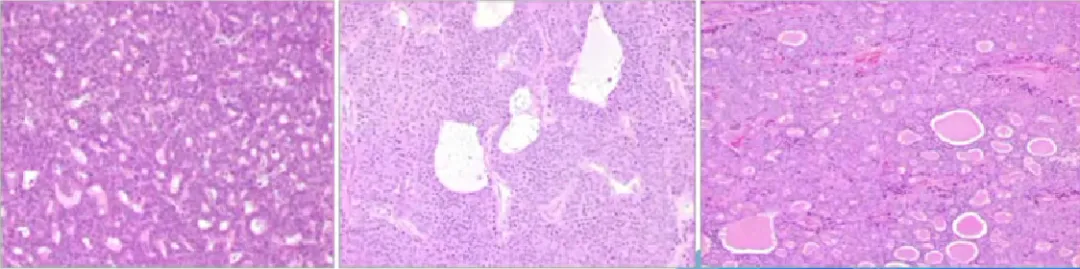

淋巴腺复合体样腺癌(Lymphoglandular complex-like adenocarcinoma)

• 罕见,也被称为穹顶癌(dome carcinoma)或gut-associated lymphoid tissue carcinoma;

• 其特征是伴有明显的淋巴组织

• 其组织学表现让人联想到淋巴腺复合体,腺体排列紊乱、促结缔组织增生、坏死和/或单个细胞,提示恶性;

• 大多数病例局限于黏膜下层或更深浸润;

• 相关分子数据较少,部分显示微卫星不稳定(MSI);

• 可能会发生淋巴结转移,但总体预后良好